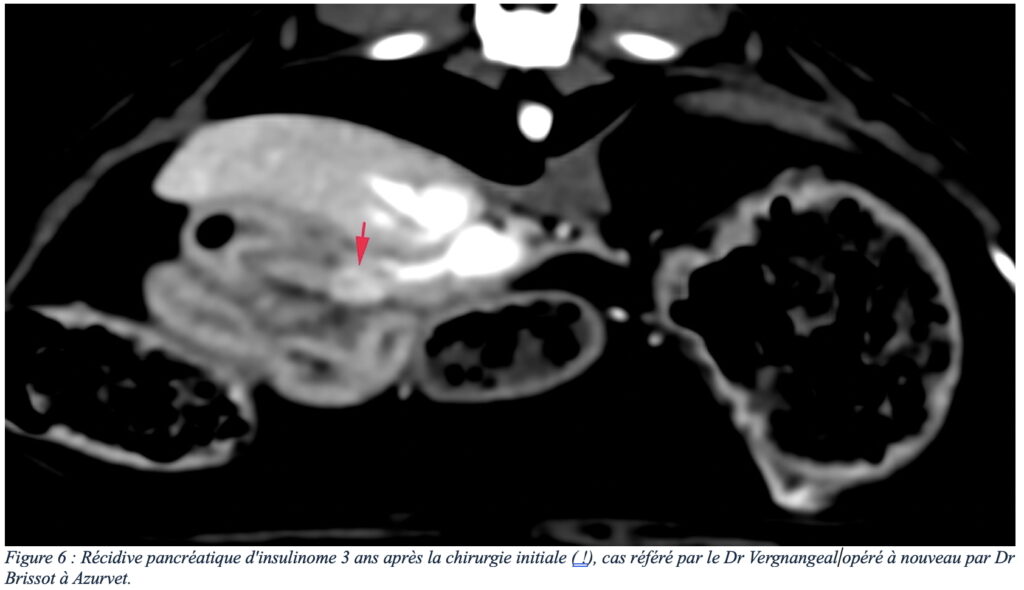

L’échographie est un examen de première intention pour l’exploration d’un insulinome. La sensibilité de l’échographie dépend de l’expérience du manipulateur, mais aussi de la conformation de l’animal (l’examen du pancréas est limité sur des chiens de grande taille et/ou avec cage thoracique profonde). Un insulinome peut se présenter dans la plupart des cas comme un nodule unique hypoéchogène de taille variable (figure 1), et de façon moins fréquente comme des nodules multiples ou une zone irrégulière plus diffuse du pancréas (2) – noter que ces lésions ne sont pas spécifiques d’un insulinome et que tout autre nodule bénin ou malin du pancréas peut avoir cette apparence et donc que la suspicion clinique/biologique est cruciale. L’échographie permet également une évaluation des nœuds lymphatiques et du foie pour un premier bilan d’extension.